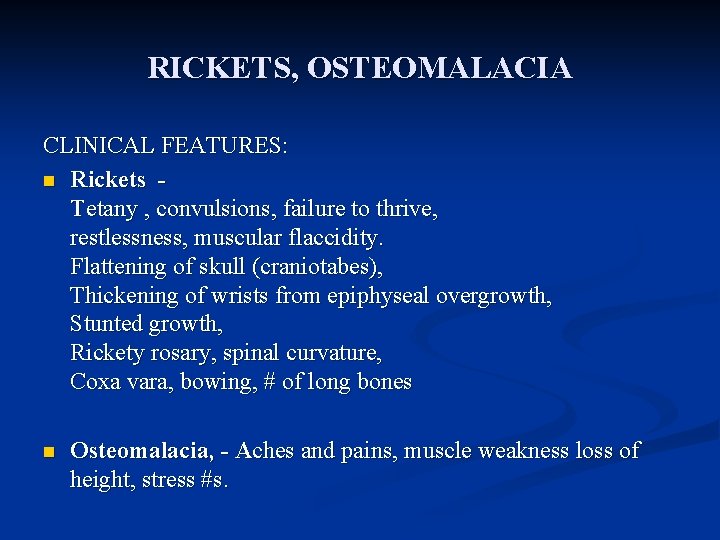

Clinical features n n n Osteomalacia in adults starts insidiously as aches and pains in the lumbar (lower back) region and thighs, spreading later to the arms and ribs. Pain is non-radiating, symmetrical, and accompanied by tenderness in the involved bones. Proximal muscles are weak, and there is difficulty in climbing up stairs and getting up from a squatting position. Physical signs include deformities like and lordosis. Pathologic fractures due to weight bearing may develop. Most of the time, the only alleged symptom is chronic and bone aches are not spontaneous but only revealed by pressure or shocks.

RICKETS, OSTEOMALACIA CLINICAL FEATURES: n Rickets - Tetany , convulsions, failure to thrive, restlessness, muscular flaccidity. Flattening of skull (craniotabes), Thickening of wrists from epiphyseal overgrowth, Stunted growth, Rickety rosary, spinal curvature, Coxa vara, bowing, # of long bones n Osteomalacia, - Aches and pains, muscle weakness loss of height, stress #s.

Manifestations of Osteomalacia Localized bone pain Difficulty walking Low back pain Fractures are common, and delayed healing occurs Muscular weakness Weight loss Progressive deformities of the spine (kyphosis)